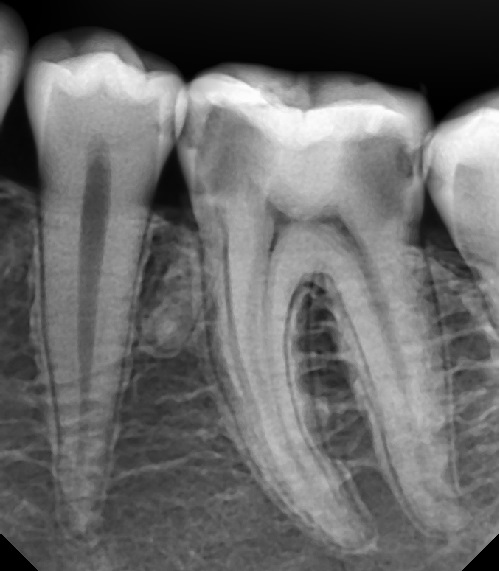

Пульпит на рентгене

Рентген кариеса зуба

Рентгенограмма кариеса

Identifying Diseases of the Teeth and Oral Cavity Through Radiographic Images Am

Прицельная внутриротовая рентгенография